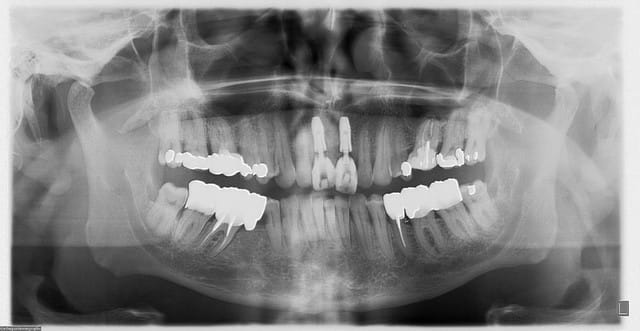

aussitôt demandé, aussitôt fait !!

(j+1 an)